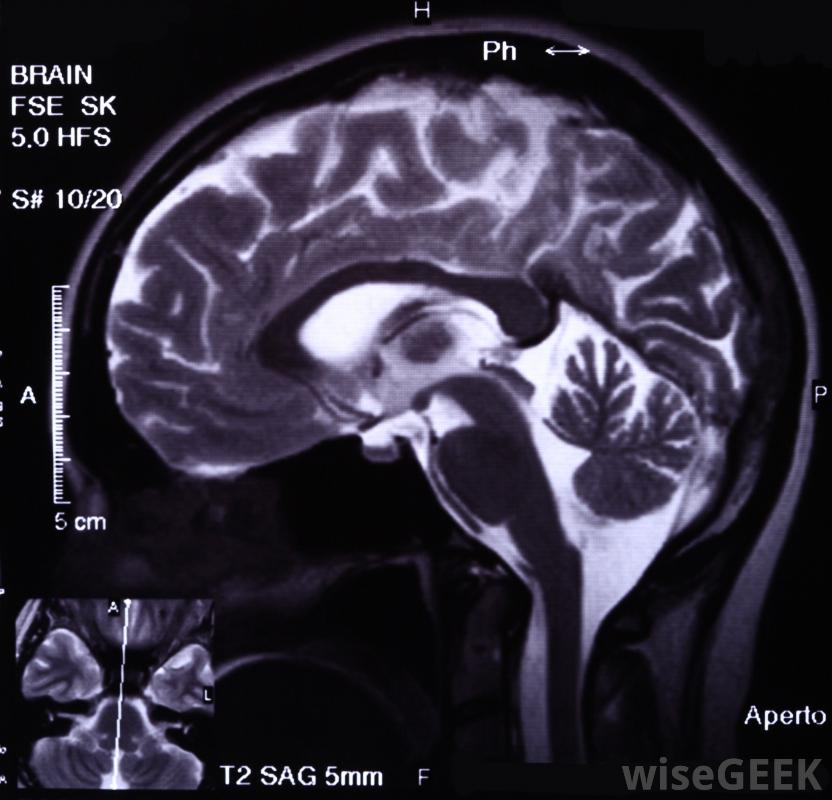

有些患者会脑膜瘤手术时需要全身麻醉,而其他人则不需要。脑膜瘤是在大脑周围的物质上形成的肿瘤,在脑膜瘤手术之前,我们将进行一系列的影像学研究,以进一步了解肿瘤及其位置,以确定是否它是可操作的。

医学成像扫描,如磁共振成像,用于定位和测量肿瘤最微创的方法是伽玛刀手术,靶向放射治疗病人的大脑,杀死肿瘤细胞对于这种类型的脑膜瘤手术,患者的头部将被拧入一个金属框架内,在颅骨周围形成四个小切口。当伽玛刀用于直接照射颅骨的右侧区域时,患者处于清醒状态。后续扫描将用于确认肿瘤已经消失。风险可能包括肿胀,可能手术刀是一种小而锋利的刀,在外科手术中用来做切口脑膜瘤手术的其他微创方法包括通过鼻内镜手术进入肿瘤。为了舒适和安全,患者将被置于麻醉下,风险略高于伽玛刀手术,因为病人除了颅内肿胀外,还会发生感染。对于颅底等疑难部位的肿瘤,可能需要更具侵袭性的切口才能到达肿瘤,而且病人的风险也会增加。